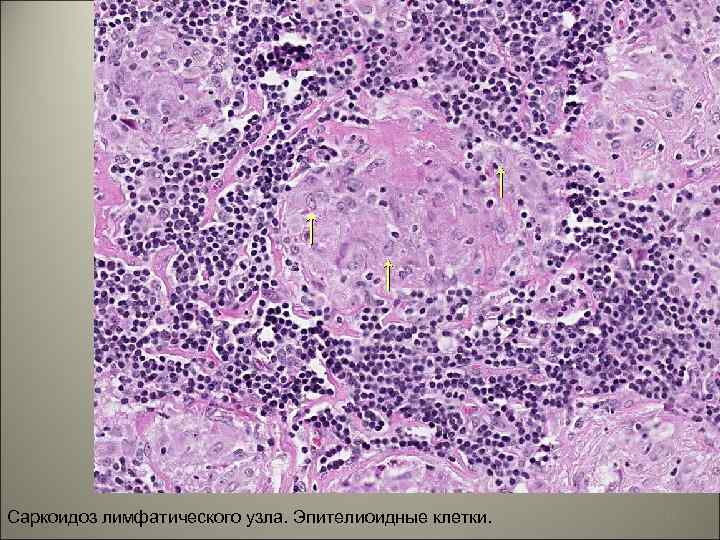

• Саркоидозные гранулемы похожи на туберкулезные, но отличаются от последних отсутствием творожистого некроза и возбудителя, а также четкими границами (т. н. «штампованные гранулемы» ). Параллельно с гранулематозным процессом происходит повреждение окружающих тканей вплоть до некрозов, которые при благоприятном течении заболевания замещаются

Саркоидоз лимфатического узла. Эпителиоидные клетки. 41

• 83. САРКОИДОЗ ШЕЙНОГО ЛИМФОУЗЛА. • В ткани лимфоузла множественные гранулемы, состоящие из эпителиоидных, лимфоидных, единичных гигантских клеток. Творожистый некроз отсутствует, границы гранулем четкие (т. н. «штампованные» гранулемы).

83. САРКОИДОЗ ШЕЙНОГО ЛИМФОУЗЛА (Х 100).

83. САРКОИДОЗ ШЕЙНОГО ЛИМФОУЗЛА (Х 400).